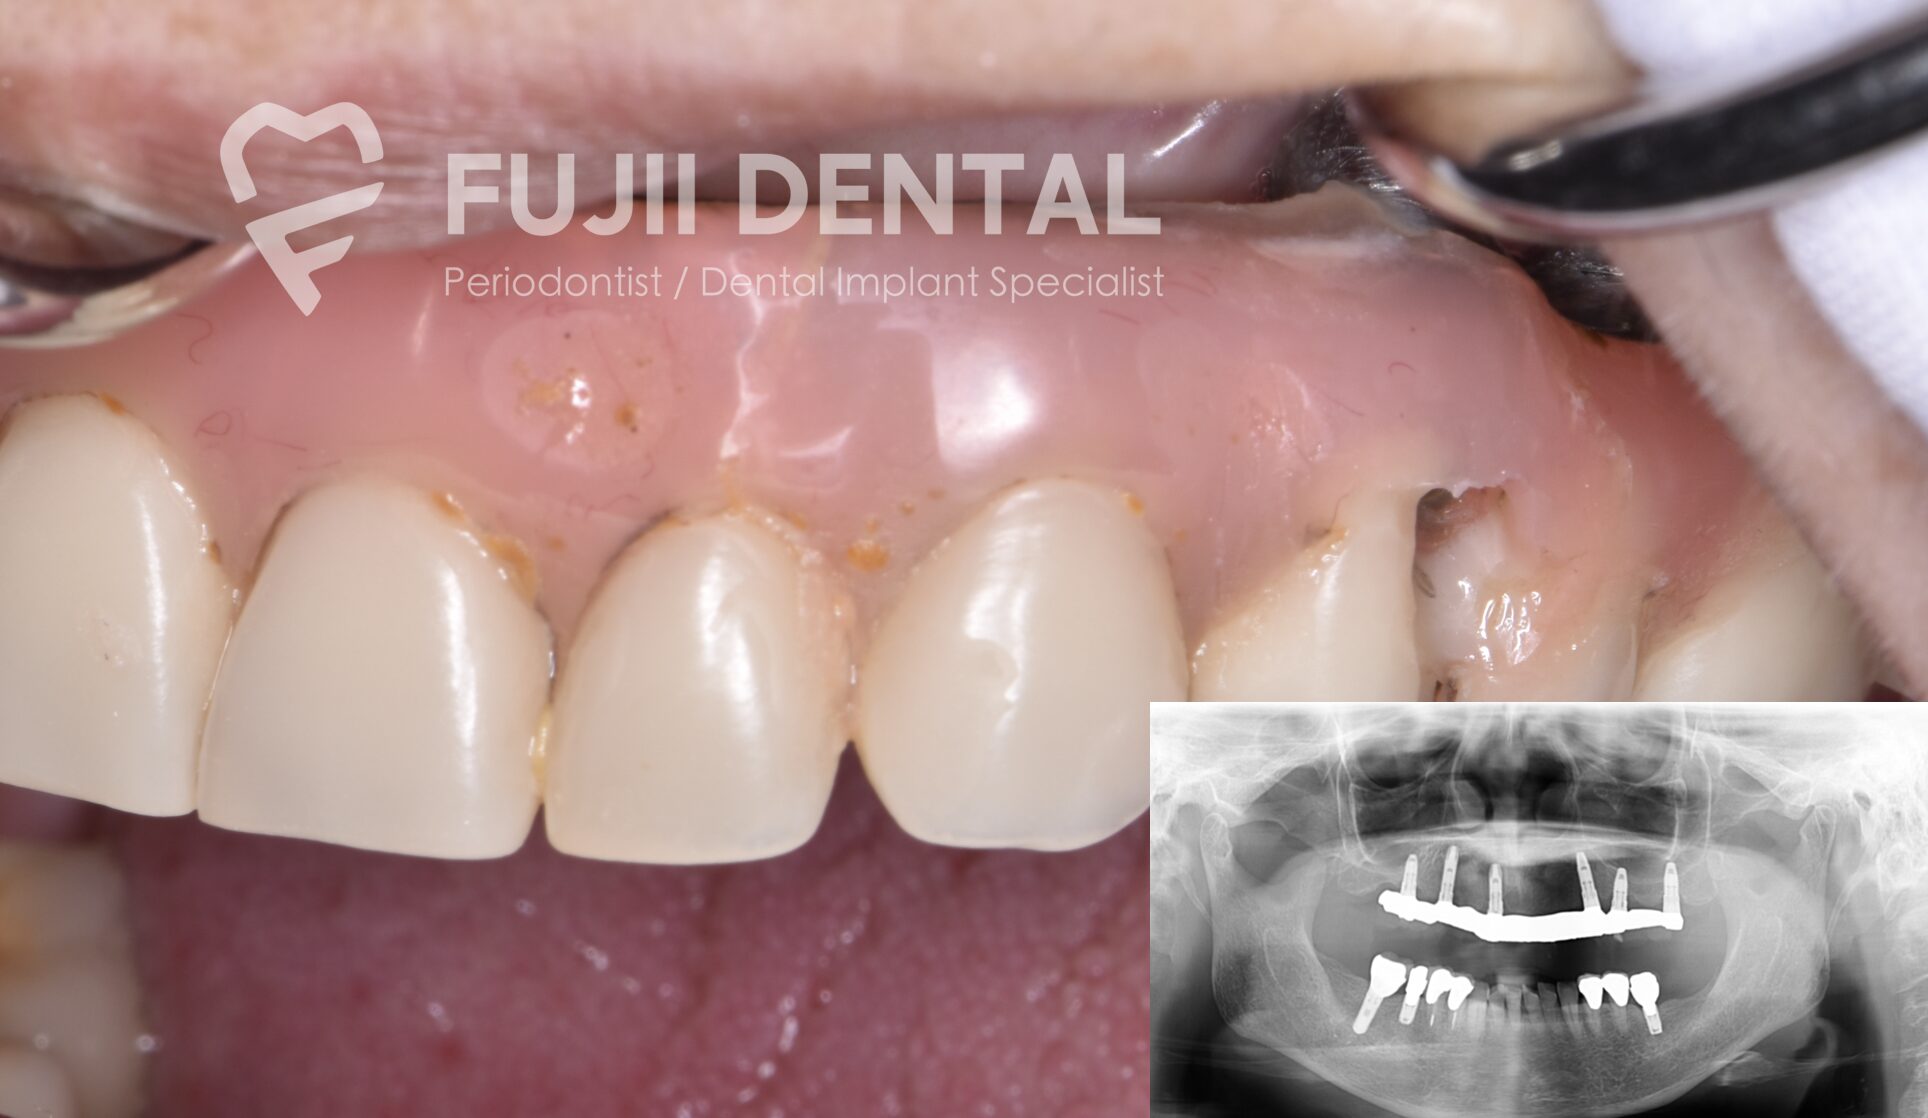

患者様は、他院にて設置されたボーンアンカードブリッジを使用されていました。補綴物の歯肉の一部分が欠けていたので来院されたのですが、、ブリッジ下面が凹んだ形状になっており、汚れがたまりやすい形状でした。

その結果、清掃が困難となり、インプラント周囲炎のリスクが高まっていました。補綴物の修理で対応するよりも、根本的に補綴物を作り直すこととなりました。